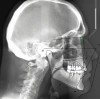

A 76-year-old, retired businessman presented to the office to improve his smile and overall oral health (Figure 1). An esthetic assessment revealed minimal display of the upper anterior teeth and dark discoloration of all teeth (Figure 2). Cephalometric analysis determined that the ANB measurement was 4°, indicating a mild Class II skeletal pattern with upright and retroclined incisors. At 145°, the interincisal angle was excessive, and at 6°, the 1-NA measurement was less than ideal (ie, 22°). If the root angulation of the upper incisors could be shifted toward the palate, it would improve the display and function of the upper anterior teeth with less restrictive anterior guidance (Figure 3).

(3.) Pretreatment cephalometric analysis.

Figure 3